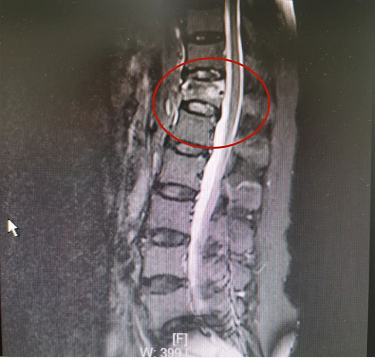

患者骨水泥椎体成形术术前影像

患者郭某,女,64岁,不慎摔倒,腰背部疼痛伴活动受限2天,休息后症状不见好转,就诊于我院脊柱科。X线片提示胸T12椎体压缩性骨折。完善术前相关检查后,来院第二天予患者行胸T12骨水泥椎体成形术,手术约30分钟后,患者自觉腰背部疼痛明显减轻。术后第二天拍片复查后,患者带腰围可下床自行活动。